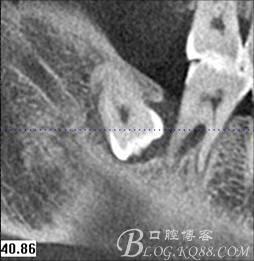

圖3.通過矢狀面和冠狀面來判斷48與下頜管及47的關系

48未萌出,47遠中可探及深約7mm的牙周袋。頰側47、48之間牙齦紅腫,有少量血性滲出。X線根尖片顯示:48牙冠反轉倒置,47遠中牙槽骨吸收明顯。CBCT顯示:48牙冠近中面位于下頜管內。

圖1. 47牙冠的近中面緊鄰下頜神經管